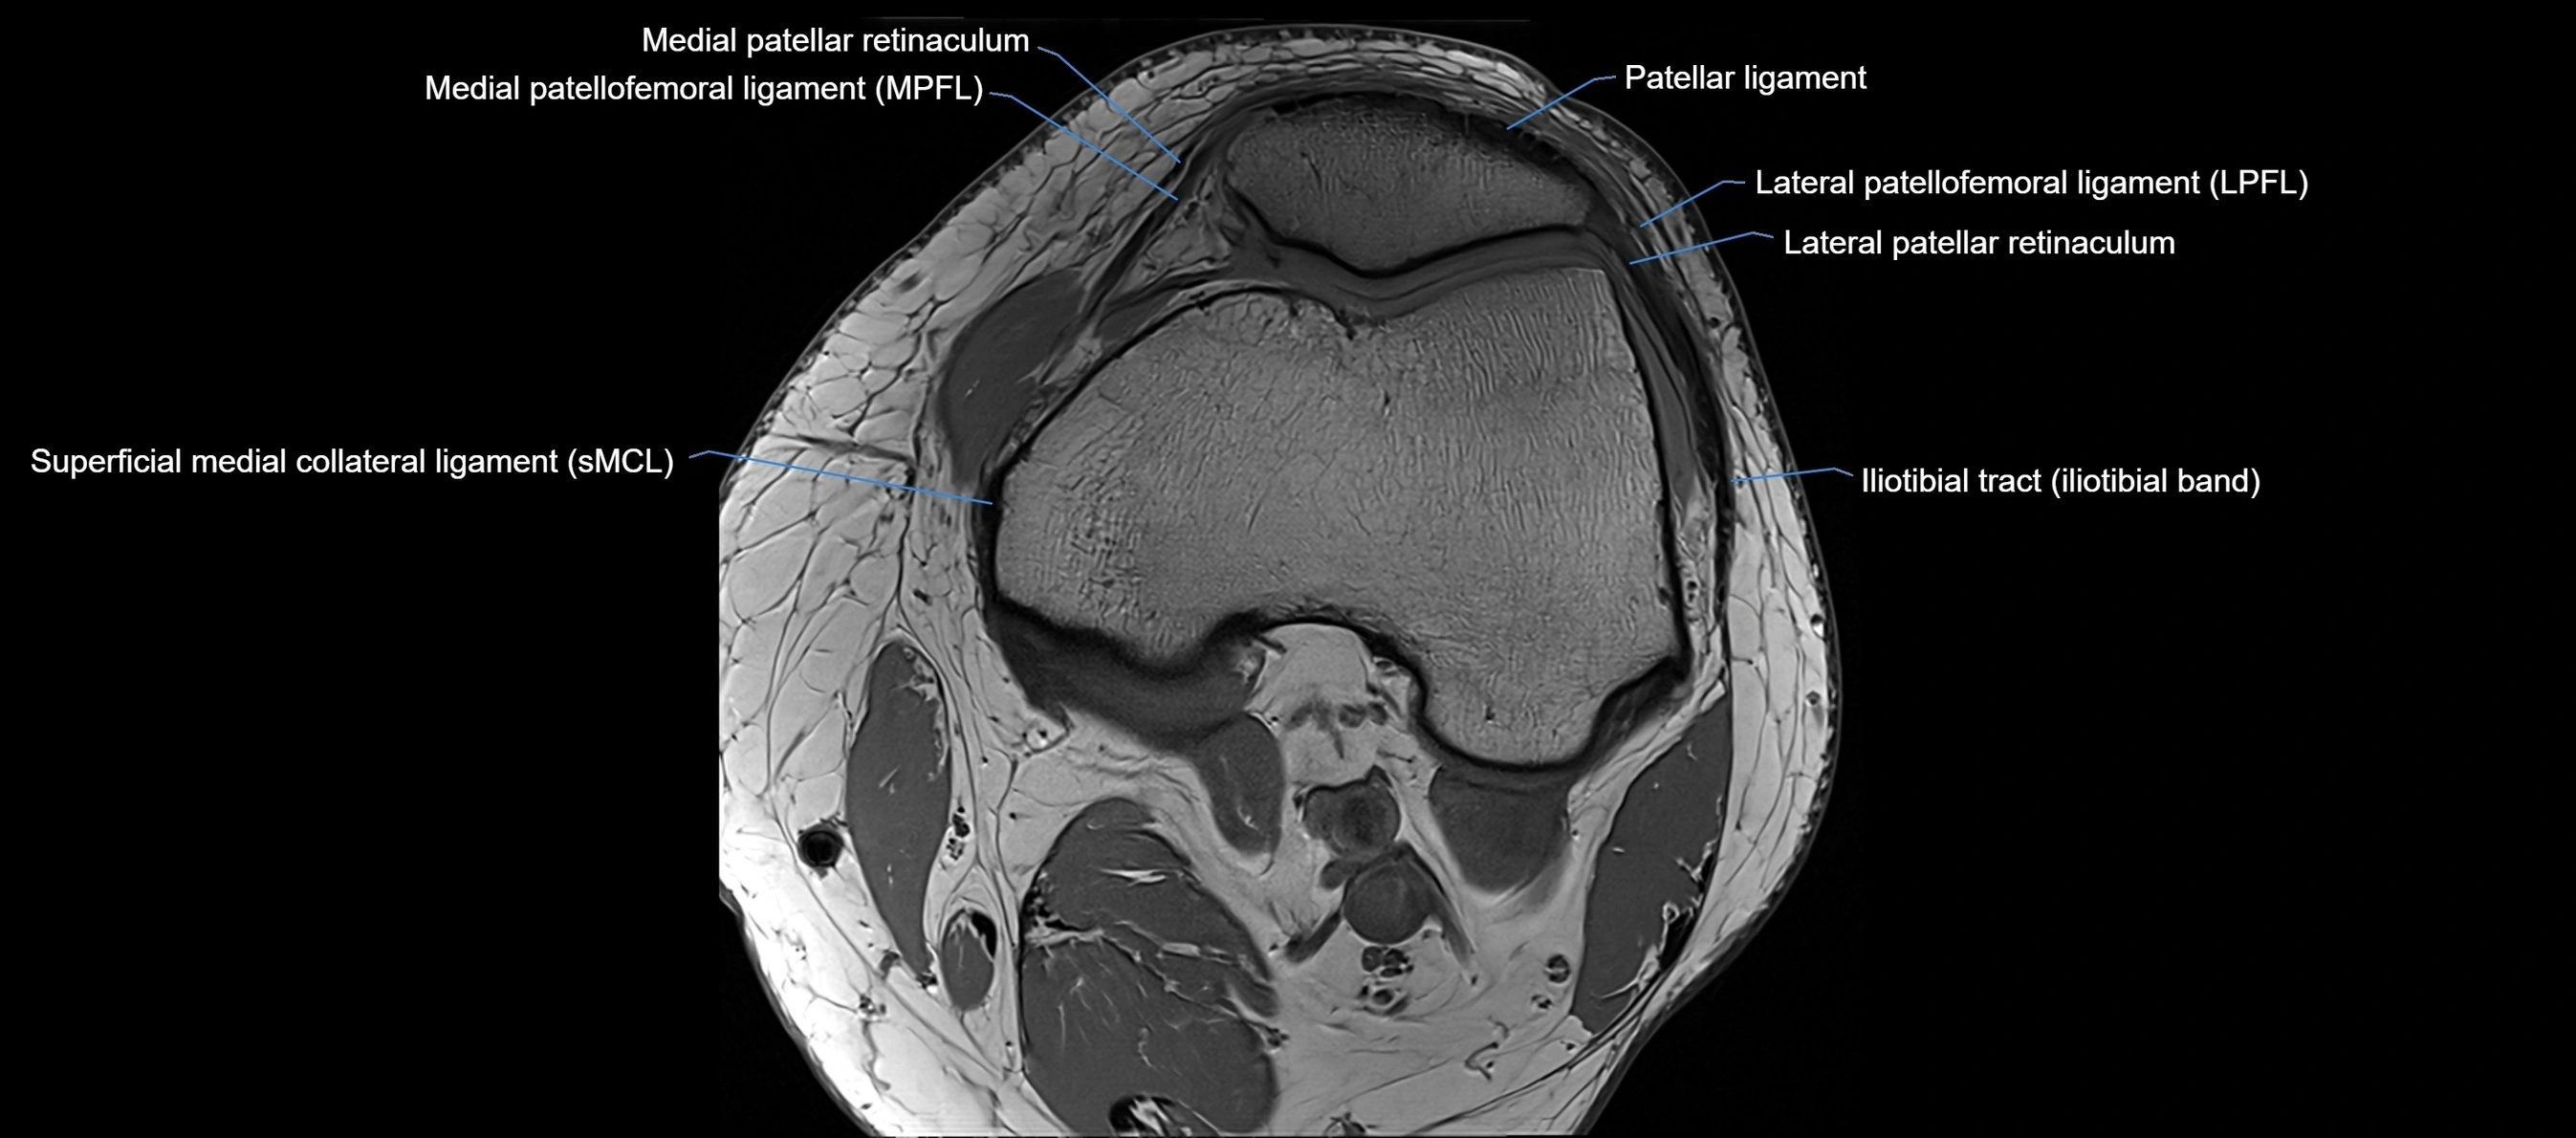

MRI images

image